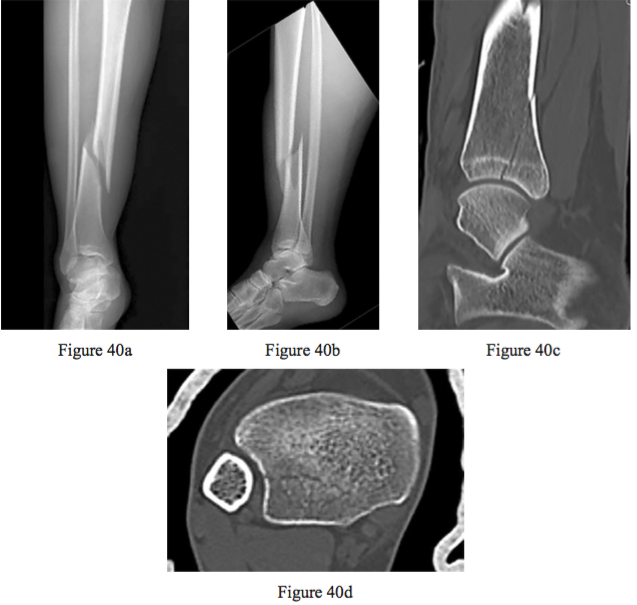

Figures 40a through 40d are the radiographs and CT scans of an 18-year-old woman who sustained a tibia/ bula fracture. Prior to intramedullary nailing of the tibia, the physician should

PREFERRED RESPONSE: 4 perform reduction and internal xation of the intra-articular split.